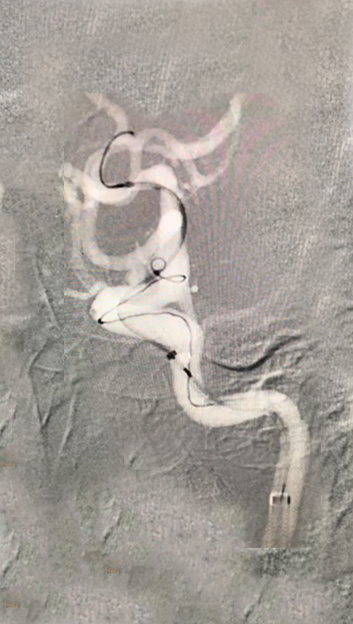

CT造影

1.1)

Echelon微导管塑形,瘤颈口到位

1.2)

Navien + Phenom助力上高到颈内动脉末端